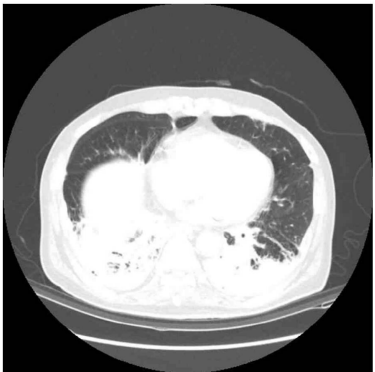

70세 남자가 4일 전부터 숨이 찬다며 병원에 왔다. 7일 전 부터 누런 가래를 동반한 기침을 한다. 1년 전 뇌경색으로 진단되어 치료를 받은 이후로 식사 때 사레가 자주 들린다고 한다. 40갑•년의 과거 흡연자이다. 혈압 120/80 mmHg, 맥박 98회/분, 호흡 24회/분, 체온 38.8°C이다. 양쪽 가슴에서 거품 소리가 들린다. 가슴 컴퓨터단층촬영 사진이다. 혈액 검사 결과는 다음과 같다. 치료는?

CT: Bilteral lower lobe consolidations

• 1년 전 뇌경색을 진단받았으므로 누워서 생활하는 비중이 많았을 것으로 판단되며, 사레가 자주 들린다는 점에서 aspiration event가 있었음을 알 수 있다. 더불어 Chest CT상 양측 폐하부 posterior portion에 consolidation이 확인되고 혈액검사상 leukocytosis, CRP 상승 등 감염을 시사하는 소견으로 보아 흡인성 폐렴을 진단할 수 있다.